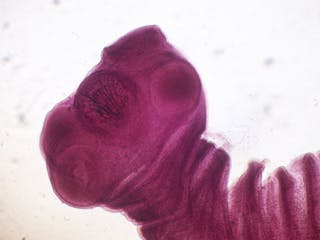

Tenia di maiale: Taenia solium

Taenia solium, nota anche come tenia di maiale, può causare crisi epilettiche e altri problemi neurologici nell’uomo dall’ingestione di uova contenenti larve infettive. La rottura del guscio dell’uovo si verifica nell’intestino, consentendo alle larve di uscire ed entrare nel flusso sanguigno. Una volta in circolazione, le larve possono depositarsi in molti tipi di tessuti corporei.

A volte le larve attraversano la barriera emato-encefalica ed entrano nel sistema nervoso centrale (SNC), dove gli embrioni si sviluppano in cisti piene di liquido che portano a una condizione nota come neurocysticercosis che si traduce in convulsioni ed è una delle infezioni parassitarie più pericolose del SNC in tutto il mondo. La diagnosi di neurocysticercosis è difficile a causa della mancanza di sintomi clinici specifici. La malattia – che normalmente colpisce persone in Sud America, Asia e Africa sub-sahariana – è stata eccezionalmente rara nei paesi occidentali, tuttavia alcuni casi sono stati segnalati nel Regno Unito e negli Stati Uniti.

Spirometro erinaceieuropae

Spirometro erinaceieuropae è una rara specie di tenia che trascorre parte della sua vita in anfibi e crostacei prima di passare a cani e gatti nella parte finale del suo ciclo vitale.

Gli esseri umani sono considerati un ospite accidentale per questa specie di vermi e mentre vivono in una persona, il parassita non raggiungerà la maturità. Le infezioni da S. erinaceieuropae – note come sparganosi – sono più probabili essere importate da aree come la Cina.

Alcuni di noi potrebbero aver sentito parlare del recente caso di un uomo britannico che ha avuto mal di testa, convulsioni e perdita di memoria per quattro anni, che in seguito è stato trovato essere causato da S. erinaceieuropae. Questo parassita è stato segnalato solo 300 volte in tutto il mondo nell’ultimo mezzo secolo e non era mai stato visto nel Regno Unito prima di quel caso.

L’infezione si acquisisce bevendo acqua contenente crostacei infetti, ingerendo rettili o rane infette crude o utilizzando un impiastro di rana cruda per curare gli occhi irritati. Le infezioni da Spirometro sono caratterizzate dalla comparsa di grandi noduli al di sotto della pelle e dal gonfiore dei muscoli che controllano il movimento oculare. L’infezione può anche coinvolgere il cervello e il midollo spinale. La diagnosi di infezione si ottiene mediante biopsia della lesione, imaging e metodi diagnostici.